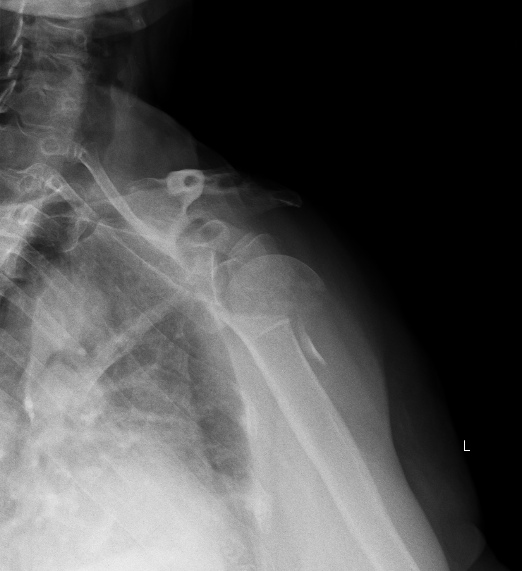

Анатолий Федорович, дорогой - чего там не видно на одном фасном снимкке,

без КТ даже? Перелом по анатомической шейке виден? Бугорки отломленные

видно? То, что суставная поверхность кнаружи-книзу смотрит, то есть

вывихнута, видно?

Остеосинтез можно сделать хоть спицами, но надо в любом случае открываться,

и не только вправить головку, но и фиксировать бугорки к плечу, то есть

сухожилия прошить хорошо. В приложении картинки с аналогичным переломом.

Вложение не в текстовом формате было извлечено&hellip;

Имя     : 2.jpg

Тип     : image/jpeg

Размер  : 44718 байтов

Описание: отсутствует

Url     : http://weborto.net:8080/pipermail/ortho/attachments/20130830/3cf8e5fd/attachment-0003.jpg